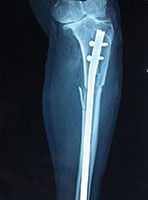

Case 4: Tibial Fracture

70 Years female fell in the bathroom and sustained injury to his left leg. She had fracture of left leg (tibia and fibula)

X-RAY 1

Pre operative x-ray showing fracture both bone left leg

X-RAY 2

Post operative Xray

X-RAY 3

Post op xray tibial fracture fixed with interlocking nail